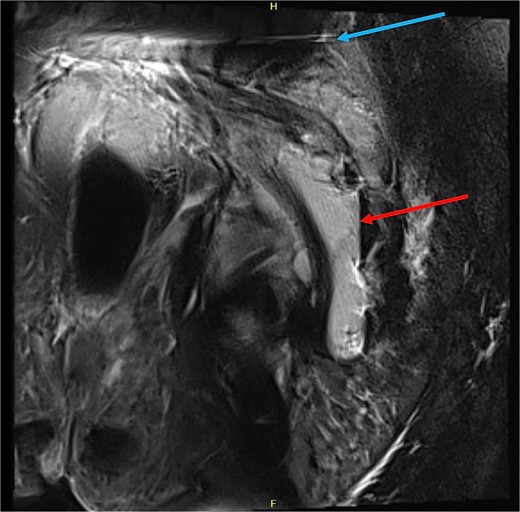

MRI pelvis (sagittal slice, patient lying lateral) demonstrating air-fluid level within the intermuscular abscess (red arrow), and artefact from SIJ screws (blue arrow).